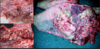

10

Q

What lesions are shown here?

A

oral vesicles and ulcers

How well did you know this?